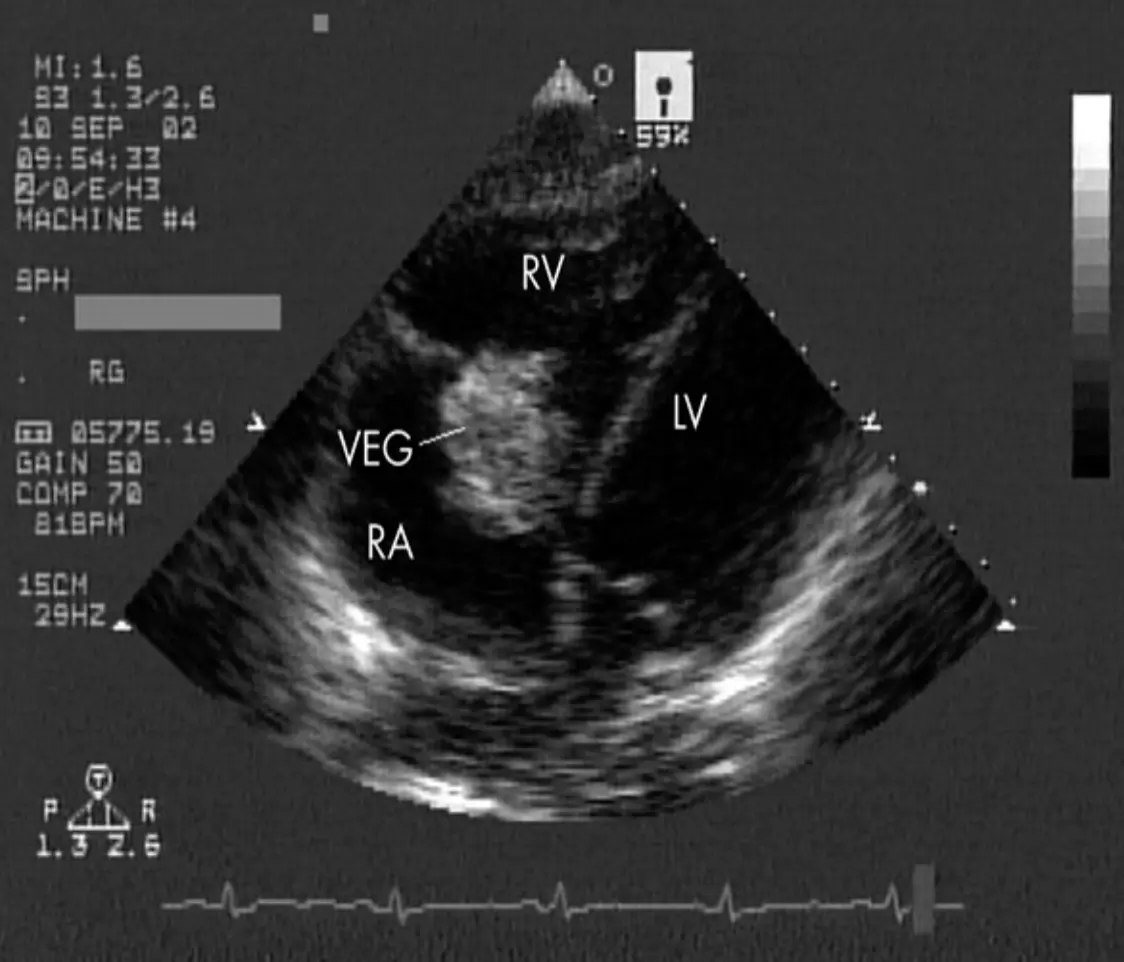

Echocardiography

- Indication: An echocardiogram for all patients with suspected IE.

- Findings: Vegetations, myocardial abscess, valve competence.

- TTE (Transthoracic): Less sensitive for vegetations than TEE; used for adolescents or overweight children.

- TEE (Transesophageal): More sensitive.

Echocardiography Images

Mitral Valve Vegetation